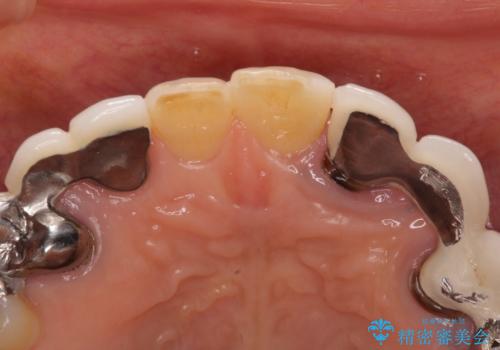

左上の歯は割れてしまっており、抜歯のうえインプラント治療が必要であり、他にも抜歯の必要な歯がある状態でした。

上顎はほぼ全ての歯をセラミッククラウンにて補綴治療を行う必要があるため、気になるデコボコや深い咬み合わせを改善するために下顎と上顎の臼歯部の矯正治療を行うこととしました。

並行して左下にはインプラントを埋入し、矯正治療を終えると同時に補綴治療を行うこととしました。